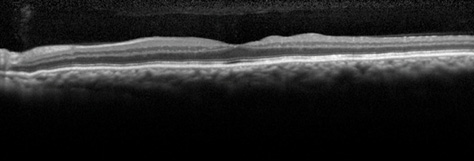

Figure 1. An OCT image of the patient's left eye shows chorioretinal folds consistent with hypotony maculopathy. Visual acuity is 20/70, and the IOP measures 3 mm Hg.

In the initial postoperative months, the patient developed a low, diffuse bleb, and the IOP decreased to 3 to 4 mm Hg OS. The bleb remained Seidel negative throughout this period. By postoperative week 10, the patient's visual acuity had decreased to 20/70 OS with an IOP of 3 mm Hg. A fundus examination revealed the presence of chorioretinal folds consistent with hypotony maculopathy, and this finding was confirmed by optical coherence tomography (OCT; Figure 1). By this time, topical steroid therapy had been discontinued in an effort to promote wound healing.